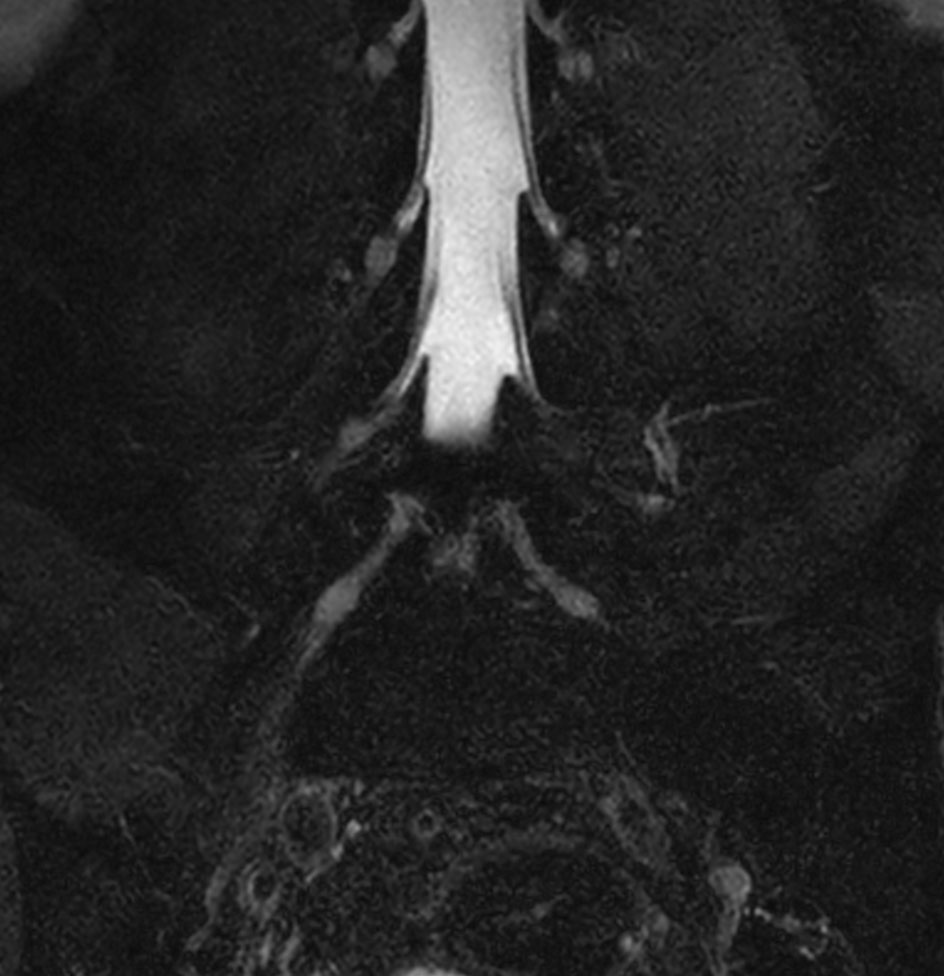

Patient with a lumbar spine bulging disc.

Coronal T2w mDIXON XD TSE (fat only)